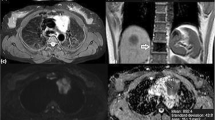

Low-risk and early thymoma in a 56-year-old woman (WHO type AB, Masaoka-Koga stage II). a Transverse T2-weighted fat-suppressed MR image shows a soft tissue mass (arrow; maximal diameter, 59 mm) in the left side of the anterior mediastinum, adjacent to the aortic arch, with well defined borders and slightly heterogeneous high signal intensity. b The ADC map of DW-MRI demonstrates grey appearance of the mass (arrow), similar to that of muscles, with a mean ADC of 1.473 × 10-3 mm2/sec (standard deviation, 0.184; minimum and maximum value, 1.037 and 1.851 × 10-3 mm2/sec, respectively). c Photomicrograph of a representative histological section detects tissue of high cellular density characterized by a mixed composition of pale lymphocyte-poor areas with spindle cell morphology (A, WHO type A component) and dark limphocyte-rich areas (B, WHO type B component). The tumour is encapsulated (C, capsule) although microscopic invasion by small clusters of tumour cells is appreciable into the thin capsule (dotted arrows) and into the surrounding mediastinal fatty tissue (arrows; F, mediastinal fat; haematoxylin and eosin stain, original magnification × 40)

High-risk and advanced thymoma in a 28-year-old woman (WHO type B3, Masaoka-Koga stage IVb for lymph node metastasis). a Transverse T2-weighted fat-suppressed MR image demonstrates an oval-shaped solid mass (arrow; maximal diameter, 91 mm) in the anterior mediastinum, adjacent to the pulmonary trunk, with intermediate and high signal intensity. b The ADC-map of DW-MRI demonstrates heterogeneous dark appearance of the mass (arrow), lower than that of muscles, with a mean ADC of 1.006 × 10-3 mm2/sec (standard deviation, 0.235; minimum and maximum value, 0.190 and 1.457 × 10-3 mm2/sec, respectively). c Photomicrograph of a representative histological section shows islands of thymoma (T) composed of a prominent population of epithelial cells mixed with a minor component of lymphocytes. Tumour cells are closely adjacent or interspersed with lung cells (L), consistent with lung invasion (haematoxylin and eosin stain, original magnification × 40)

High-risk and early thymoma in a 50-year-old man (WHO type B2, Masaoka-Koga stage IIb). a Axial T2-weighted fat-suppressed MR image detects an oval-shaped unilateral soft tissue mass (arrow; maximal diameter, 74 mm), adjacent to the aortic arch, with lobulated margins and slightly heterogeneous high signal intensity. b The ADC-map of DW-MRI demonstrates heterogeneous dark appearance of the mass (arrow) with a mean ADC of 1.175 × 10-3 mm2/sec (standard deviation, 0.289; minimum and maximum value, 0.289 and 2.072 × 10-3 mm2/sec, respectively). c Photomicrograph of a representative histological section shows a tissue of high cellular density characterized by mixed composition of lymphocytes and predominant epithelial cells resembling the normal thymic cortex. The tumour is completely encapsulated (C, capsule) and microscopic areas of tumour cells are appreciable into the thick capsule (haematoxylin and eosin stain, original magnification × 40)